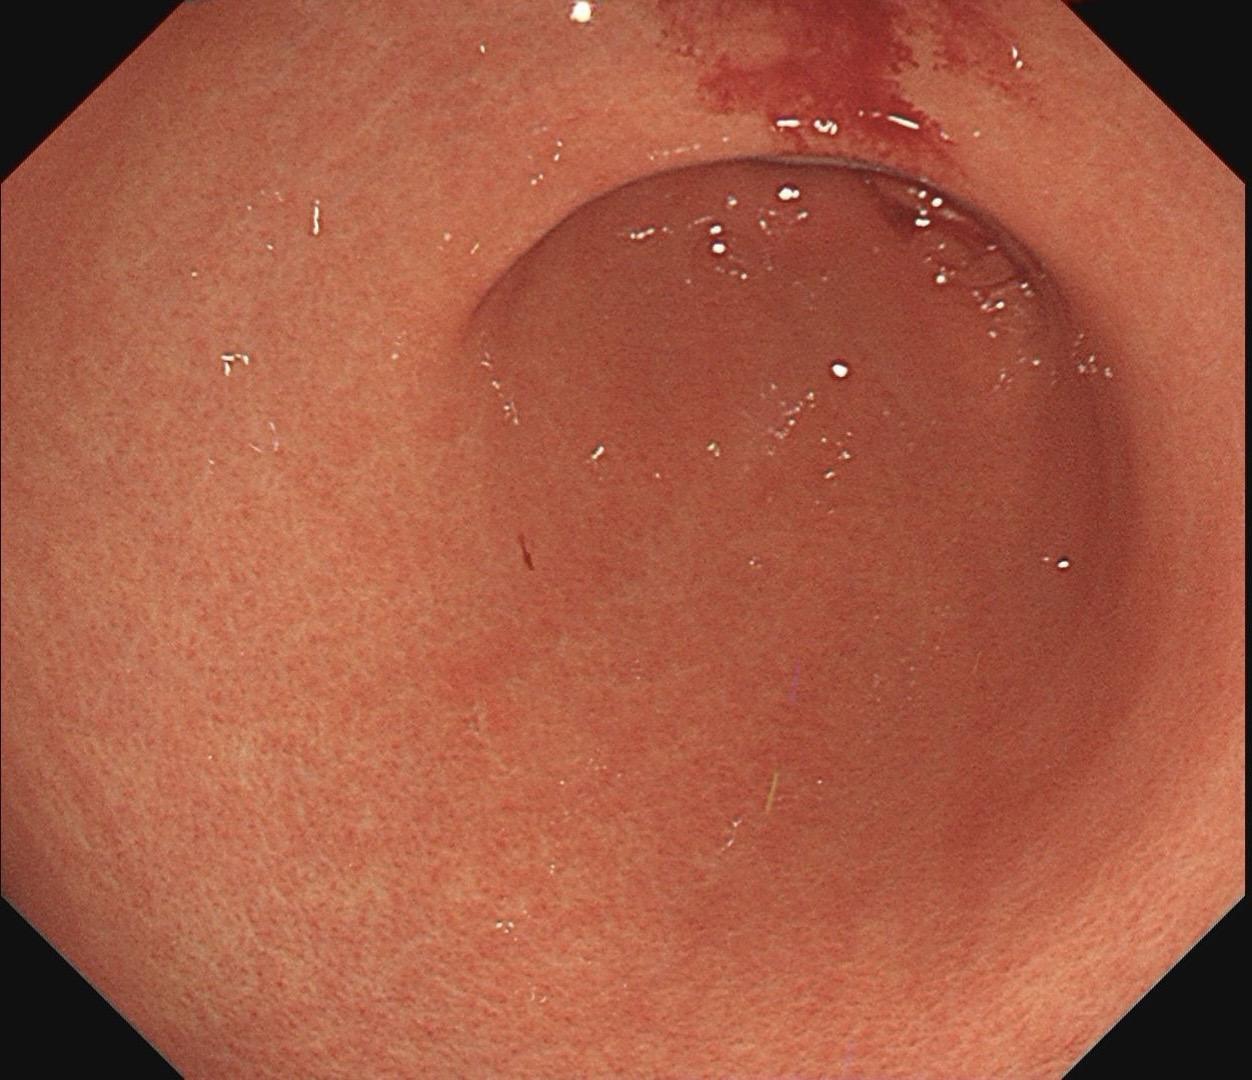

小小的糜烂一枚。这样的病灶,就算结果是阴性的,也很有意义~

萎缩背景中的褪色调。泾清渭浊,匪恃目明,静验其枢。